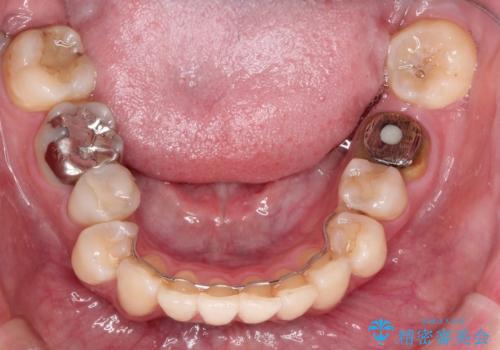

[ 放置し内部で大きく進行した虫歯 ] 神経を守るセラミック治療

担当医 大元洋佑